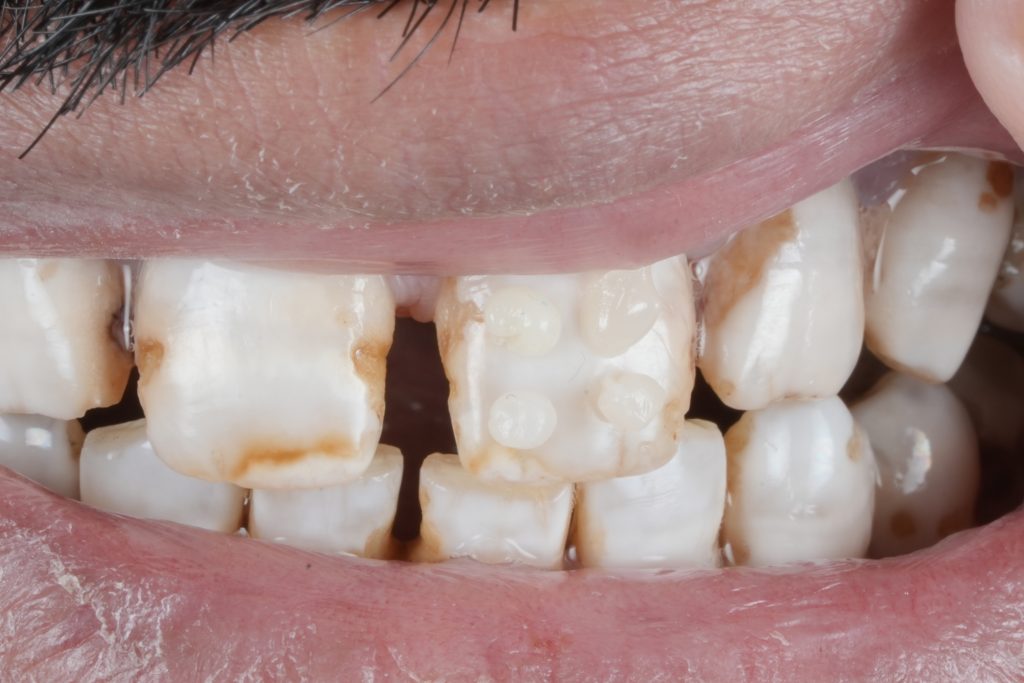

True esthetic dentistry does not begin with restorative materials or ceramic selection. It begins with understanding the condition of the enamel itself. Under proper isolation and magnification, enamel reveals a detailed narrative of demineralisation, developmental defects, discoloration, and marginal compromise that is often masked in routine clinical settings. This article highlights the importance of slowing down, isolating properly, and respecting biological principles to achieve predictable diagnosis, planning, and long-term restorative success.

Modern dentistry often moves fast. Digital workflows, restorative materials, and cosmetic demands can overshadow the most critical diagnostic step: reading the enamel. When teeth are isolated properly and viewed under magnification, enamel becomes a diagnostic map rather than a simple surface.

Demineralised zones, hypoplastic defects, marginal breakdown, and color discrepancies are frequently underestimated when examined without isolation. These subtle findings play a decisive role in treatment planning and directly influence restorative longevity.